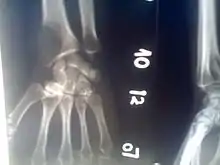

Osteolytic lesion at the bottom of the radius, diagnosed by a darker section that indicates a loss of bone density.

The most common cancers that metastasize to form osteolytic lesions are thyroid, lung, kidney, gastrointestinal, malignant melanoma and breast, though any cancer can cause bone lesions. Lesions are most often found in larger bones, such as the skull, pelvis, radius, and femur.[3][4]